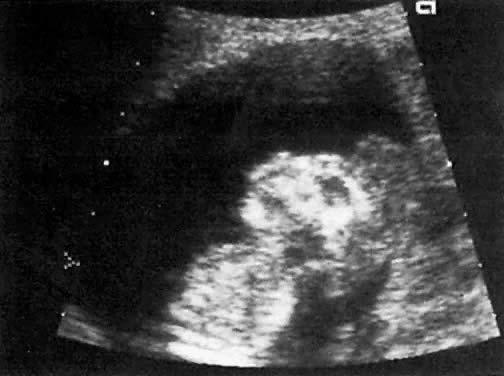

Obstruction at the level of the aqueduct of Sylvius results in enlargement of the third and lateral ventricles (Fig. 23). The etiology of such obstruction includes (1) X-linked recessive inheritance, (2) infection with cytomegalovirus or toxoplasmosis, and (3) other lesions that impinge on the area.

Fig. 23. A. Head echogram of a fetus with hydrocephalus and dilation of the lateral ventricle. The ratio between the distance from the midline to (1) ventricular wall (+), and (2) inner aspect of the parietal bone(x) is used to assess severity of the condition. In this fetus, the ratio is 67% (normal is approximately 35%) . Note compression of the choroid plexus adjacent tot he ventricular wall and to the left of the + sign. B. Head echogram of fetus with hydrocephalus, showing dilation of the ventricular atria (+ and X, respectively). Each atrium measures 2.3 cm (normal, 0.2 to 1.0 cm)

In contrast to simple ventriculomegaly, hydrocephalus usually is more progressive, and it is frequently associated with compression of the choroid plexus (see Fig. 23).

The progression of hydrocephalus may be gauged by (1) the ventricular:hemispheric ratio, and (2) the diameter of the ventricular atrium (see Fig. 22 and Fig. 23).66, ,68 Dilation of the ventricular atrium is also a characteristic finding in agenesis of the corpus callosum. In such cases, the third ventricle is displaced cephalad and the frontal horns laterally.69